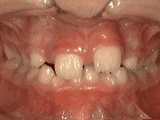

症状表现:牙齿过多,牙槽骨过窄,使牙齿没有足够空间生长就会造成牙齿排列不齐,需根据情况判断是否拔牙。

症状表现:通俗来讲就是咬牙时无法紧闭,上下牙齿中间有缝。

症状表现:上牙边沿覆盖下牙超过1/3,俗话说的天包地。